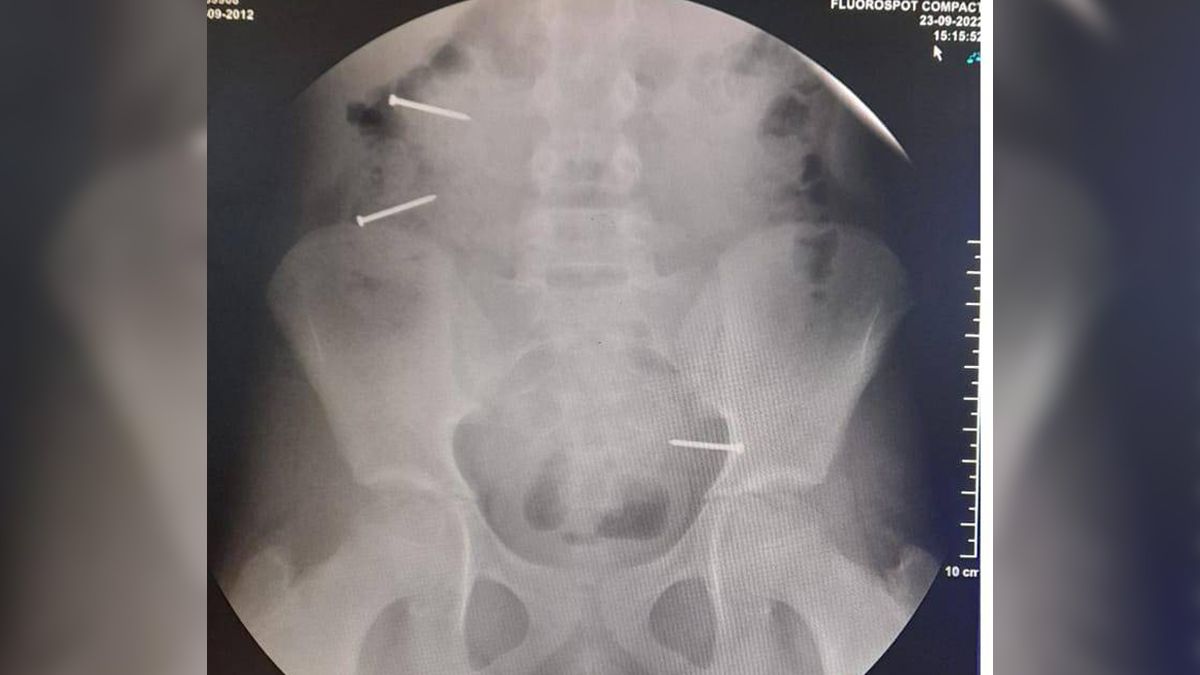

Primeramente, los médicos le realizaron una placa radiográfica observando tres clavos de importante tamaño dentro de su estómago, lo que generó una gran preocupación en sus padres y familiares. La pequeña sufrió un delicado cuadro gastrointestinal y continúa internada para los controles evolutivos.